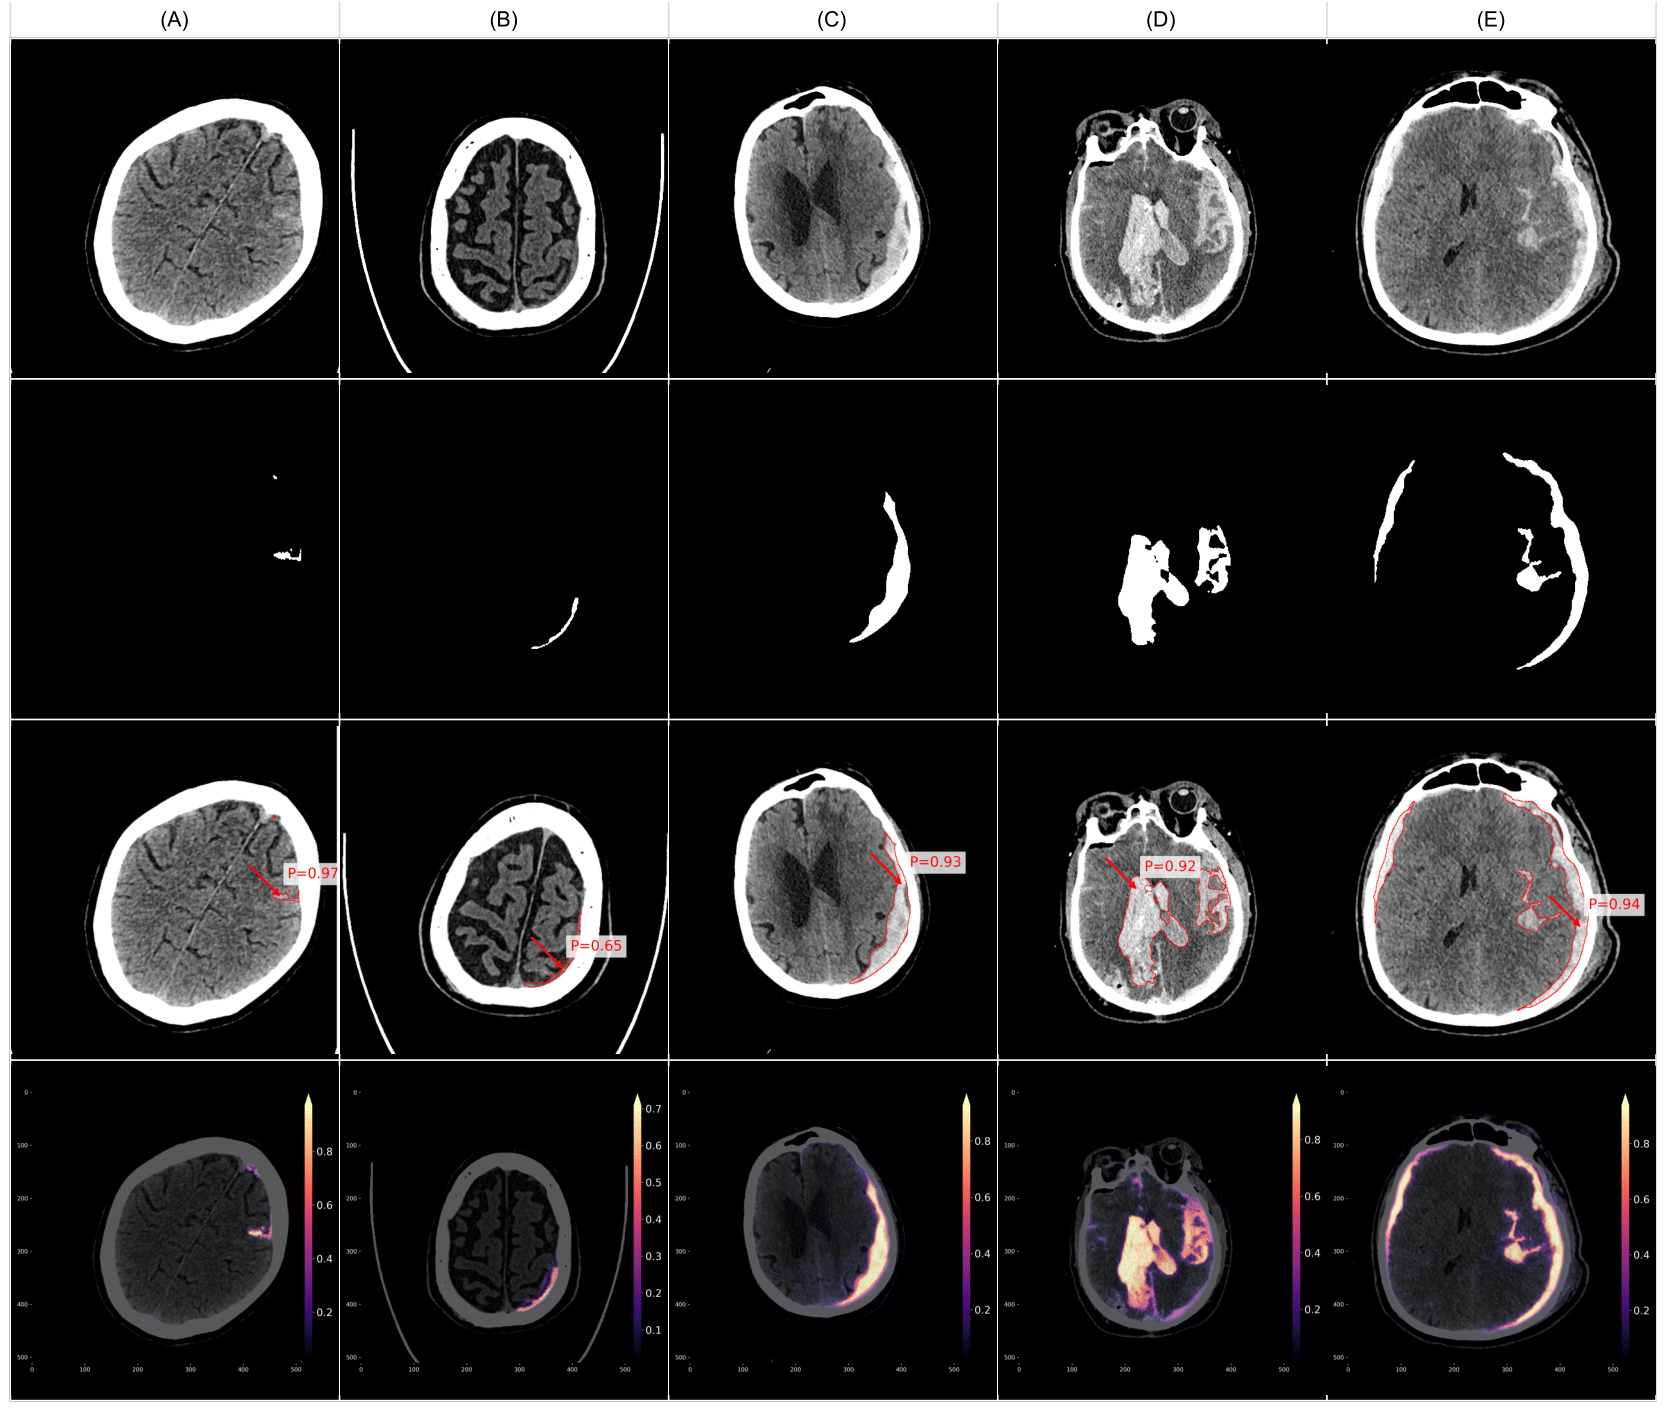

To provide a more intuitive understanding of VIOLA-AI’s performance, we have selected several representative cases for illustration, i.e., True positive case examples (Figure 9), False positive case examples (Figure 10), and False negative case examples (Figure 11).

Figure 9 presents examples of true positive cases where VIOLA-AI successfully detected intracranial hemorrhage in CT scans. Specifically, (A) and (B) illustrate smaller ICH, (C) depicts acute SDH, (D) shows a combination of SAH, IPH, and IVH, and (E) highlights both acute SDH and SAH. These images showcase the model’s capability to accurately detect a range of hemorrhage types and volumes, underscoring its high sensitivity and precision in identifying positive cases.